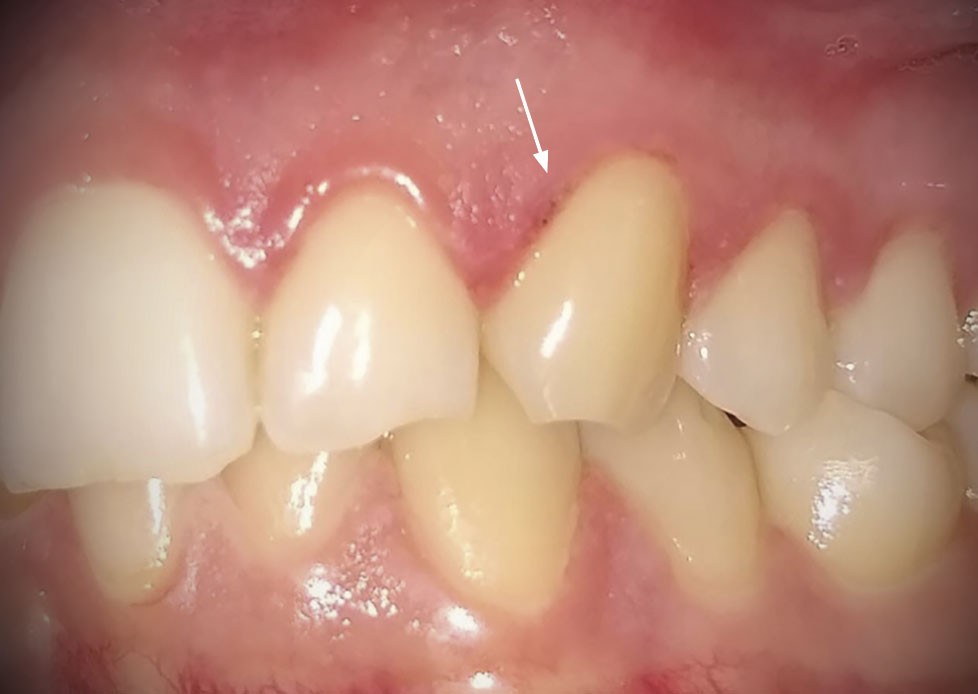

Présence de zones d’érosions post-vésiculeuses regroupées en « bouquet » en palatin des 12, 11 et 22 (fig. 1a) et au niveau de la gencive marginale de la 23 (fig. 1b). Les muqueuses affectées étaient enflammées et sensibles au toucher. Pas d’adénopathie cervico-faciale palpable et pas d’atteinte extra-orale.